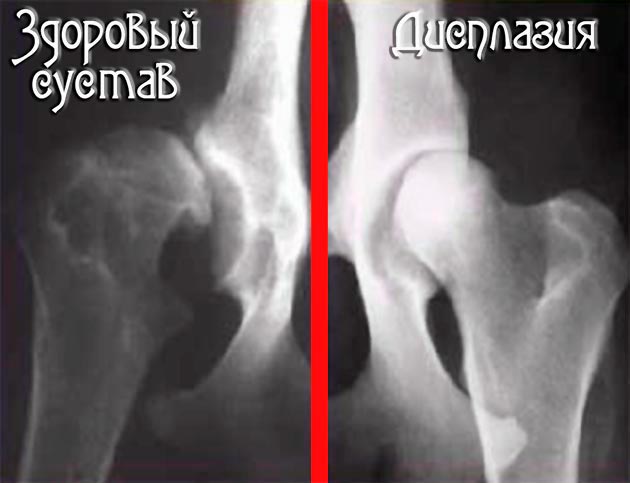

- דיספלזיה של מפרק הירך.

דיספלזיה של מפרק הירך היא בעיה נפוצה מאוד בבוסרון. בתחילה, הכלב מתחיל לצלוע, ומופיעים כאבים בעת הליכה או ריצה. ללא טיפול מתאים, המצב עלול להוביל לחוסר תנועה.